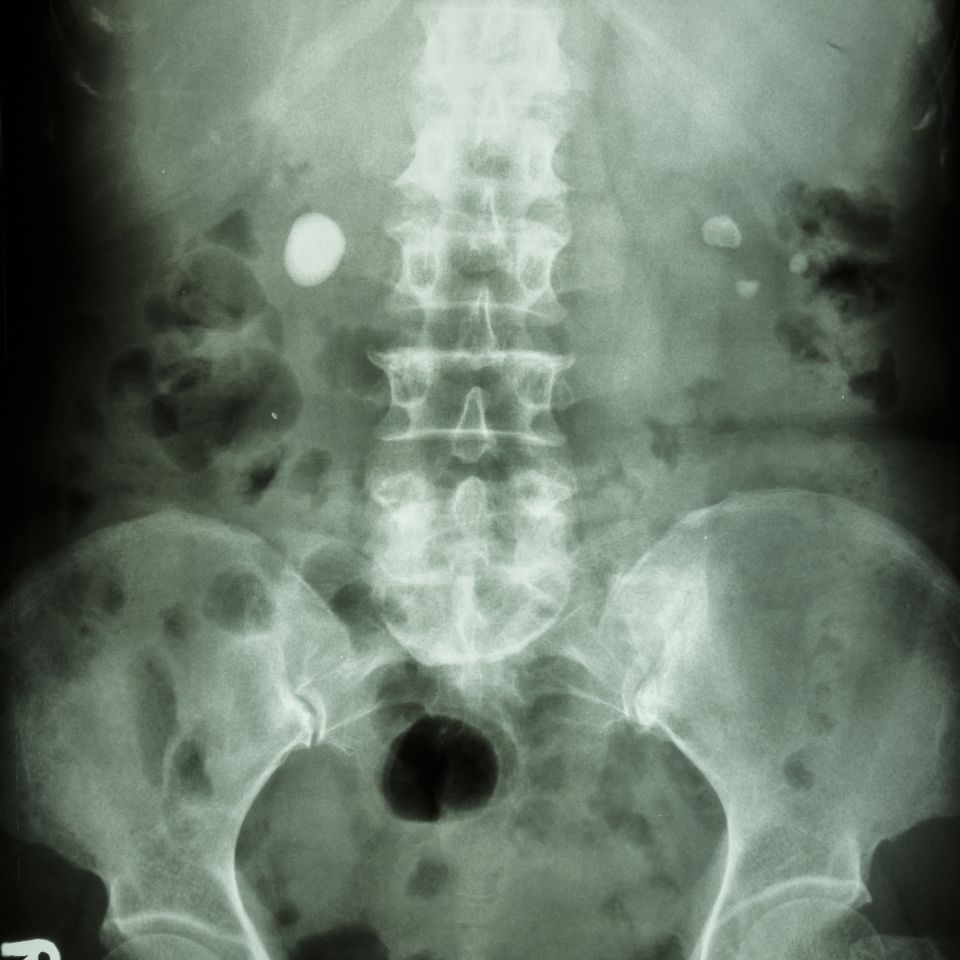

Diagnostyka obustronnej kamicy moczowodowej opiera się przede wszystkim na badaniach obrazowych. Ultrasonografia pozwala wykryć cechy zastoju moczu po obu stronach, natomiast tomografia komputerowa bez kontrastu umożliwia dokładne określenie liczby, wielkości i lokalizacji kamieni. Równolegle ocenia się parametry nerkowe w badaniach laboratoryjnych, ponieważ ich szybkie pogarszanie się jest jednym z kluczowych sygnałów alarmowych.